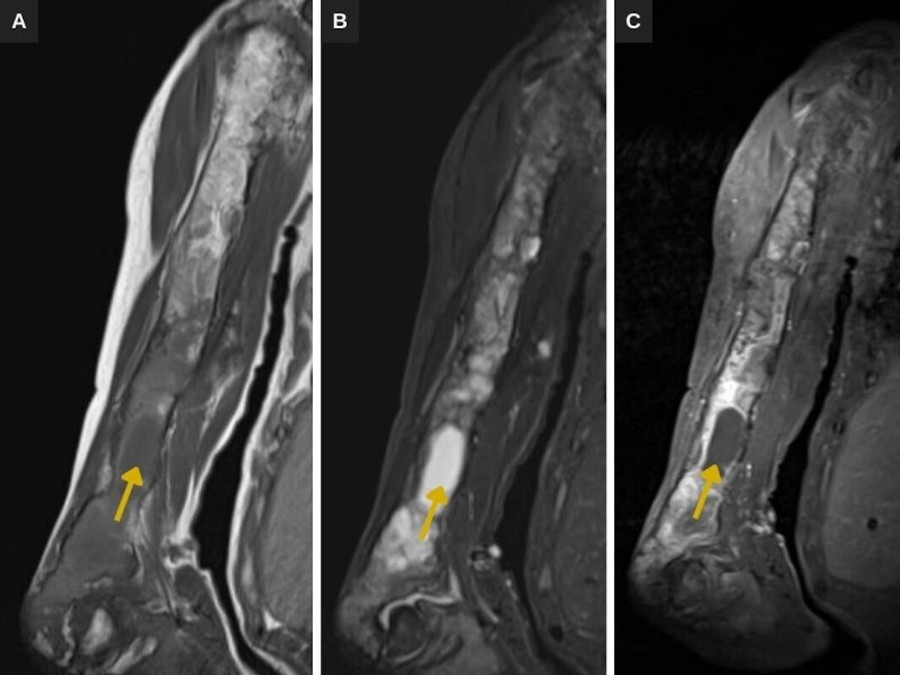

La displasia fibrosa asocia deformidad ósea y fracturas patológicas (Fig. 3). Los estudios radiológicos ponen de manifiesto el patrón en densidad mixta, con sectores en vidrio deslustrado, expansión y festoneado endostal (Fig. 3). En la RM las lesiones presentan señal heterogénea potenciada en T1 y T2, con sectores quísticos y captación heterogénea del contraste (Fig. 4).

Las técnicas de imagen son importantes para el diagnóstico y el seguimiento. Las radiografías y la TC de nuestro caso ponen de manifiesto los cambios óseos compatibles con displasia fibrosa: lesiones intramedulares, expansivas, de densidad mixta, con sectores en vidrio deslustrado característico de las lesiones fibrosas, que determinan festoneado endostal. En la RM presentan señal y captación heterogénea, predominantemente baja potenciada en T1 y de intermedia a alta en T2/STIR, con sectores quísticos. Si bien se evidencian deformidad ósea y fracturas patológicas como complicaciones de la displasia fibrosa, no se identifican signos sugestivos de transformación maligna.